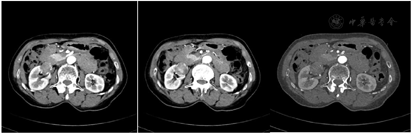

病例2专科检查:双肾区无隆起,双肾及输尿管移行区无叩压痛,膀胱区不充盈,无压痛。2021年5月11日多排CT肾肿瘤CTA(优维显)。CT所见:右肾下极内部见一约3.4 cm×3.0 cm×3.0 cm大小的异常强化灶,病灶边界尚清晰,局部膨出于肾脏表面,边缘见钙化灶,动脉期明显不均匀强化,CT值约160 HU,静脉期CT值约137 HU。腹主动脉前壁分出一支副肾动脉(A)走行至右肾下极前部,远段供应肿瘤。右主肾动脉远段近肾门处分成前、后两分支:前支:先分出一细小分支,供应右肾上极内侧,后分为上、下两分支:前-上支:供应右肾上极前部。前-下分支:供应右肾上极中部。后支:分为上、下两支。后-上支:供应右肾中上极后部。后-下支:供应右肾下极后部。印象及建议:右肾下极内侧部占位,考虑肾细胞癌(透明细胞癌),右侧副肾动脉供应肿瘤(图6)。